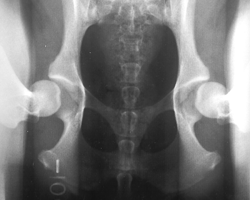

The PennHIP method is a novel way to assess, measure and interpret hip joint laxity. It consists of three separate radiographs: the distraction view, thecompression view and the hip-extended view. The distraction view and compression view are used to obtain accurate and precise measurements of joint laxity and congruity. The hip-extended view is used to obtain supplementary information regarding the existence of osteoarthritis (OA) of the hip joint. (The hip-extended view is the conventional radiographic view used to evaluate the integrity of the canine hip joint.) The PennHIP technique is more accurate than the current standard, and it has been shown to be a better predictor for the onset of OA.

The radiographs pictured here are of the same dog, yet the hip joint laxities in each view look very different. Notice that the hips in the distraction view appear to be much looser than they do in the hip-extended view.

Distraction View Compression View Hip-Extended View

The looser the joint on the distraction view, the greater is the chance that the hip will develop OA. The hip-extended view tends to mask true hip joint laxity because the joint capsule is wound up into a tightened orientation when the hips are extended. This explains why measurable joint laxity on the distraction view is always greater than the measurable laxity from the hip-extended view. In fact, distraction laxity is up to 11 times greater depending on the breed of dog under study.